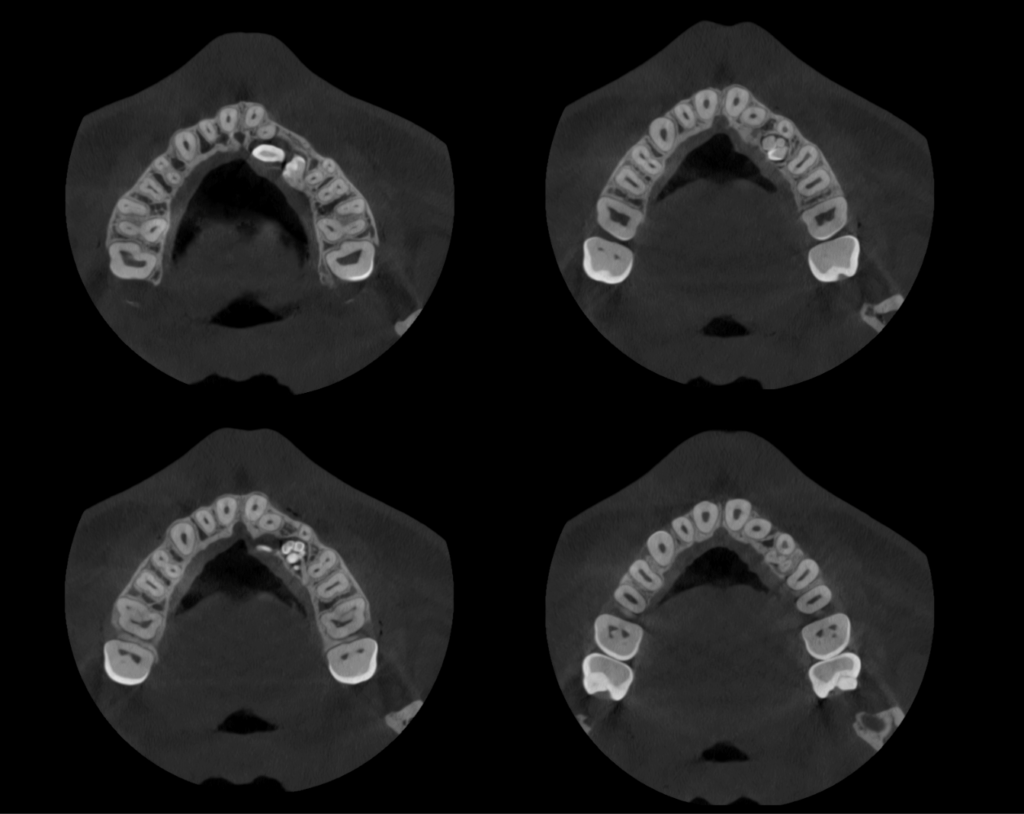

En las reconstrucciones 3D se representa de manera didáctica odontoma compuesto. (Figura 4).

RECONSTRUCCIÓN 3D